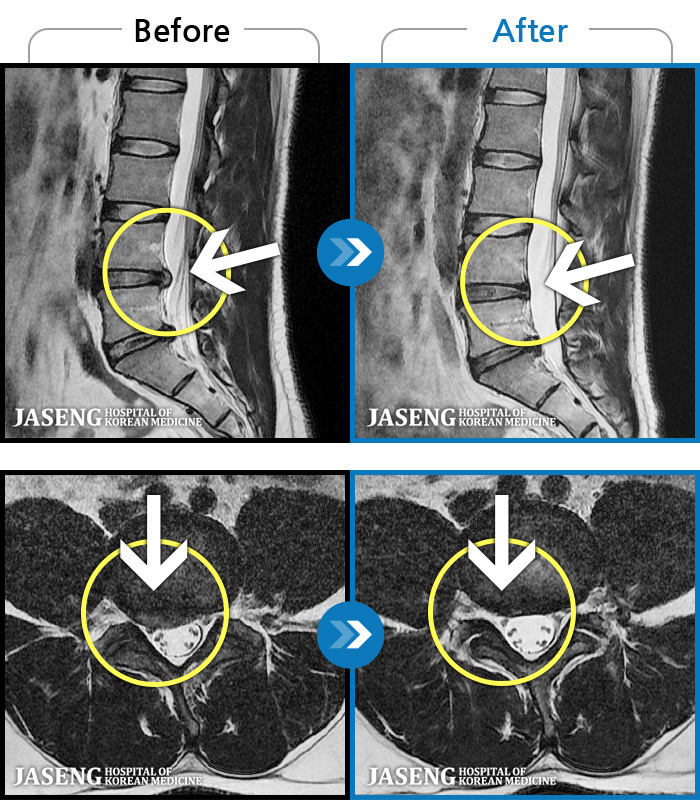

[] 03.04.01~09.11.01